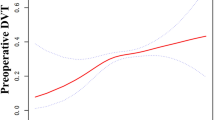

Curve fitting and analysis of threshold effect

As shown in Fig. 2, there was a linear association between admission MCV and DVT after adjusting for confounding factors. We compared the binary logistic regression model (by stand linear regression) and generalized additive model (two-piecewise linear regression) to explain this association (Table 4), and we observed the inflection point value was 97.9 in the model. However, the P for the log-likelihood ratio test was 0.110. It was better to explain the relationship between MCV and DVT by the linear association at present.